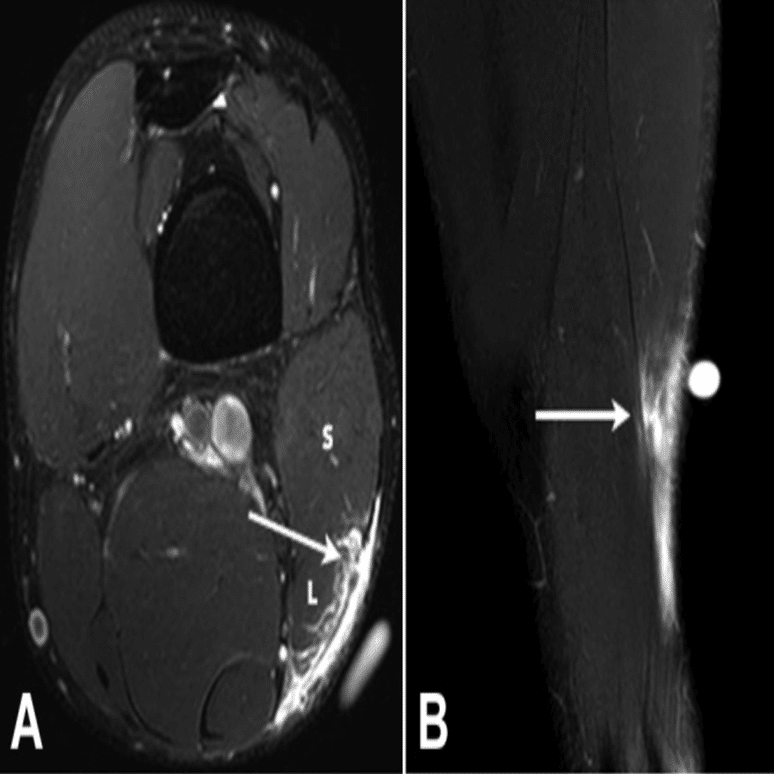

・Ⅱ型3度

(Pedret C, J Belg Soc Radiol. 2022から引用)

全周性に腱膜の連続性が確認できない

(奥脇 透:大腿二頭筋肉ばなれの MRI 分類、臨床スポーツ、2019より引用)